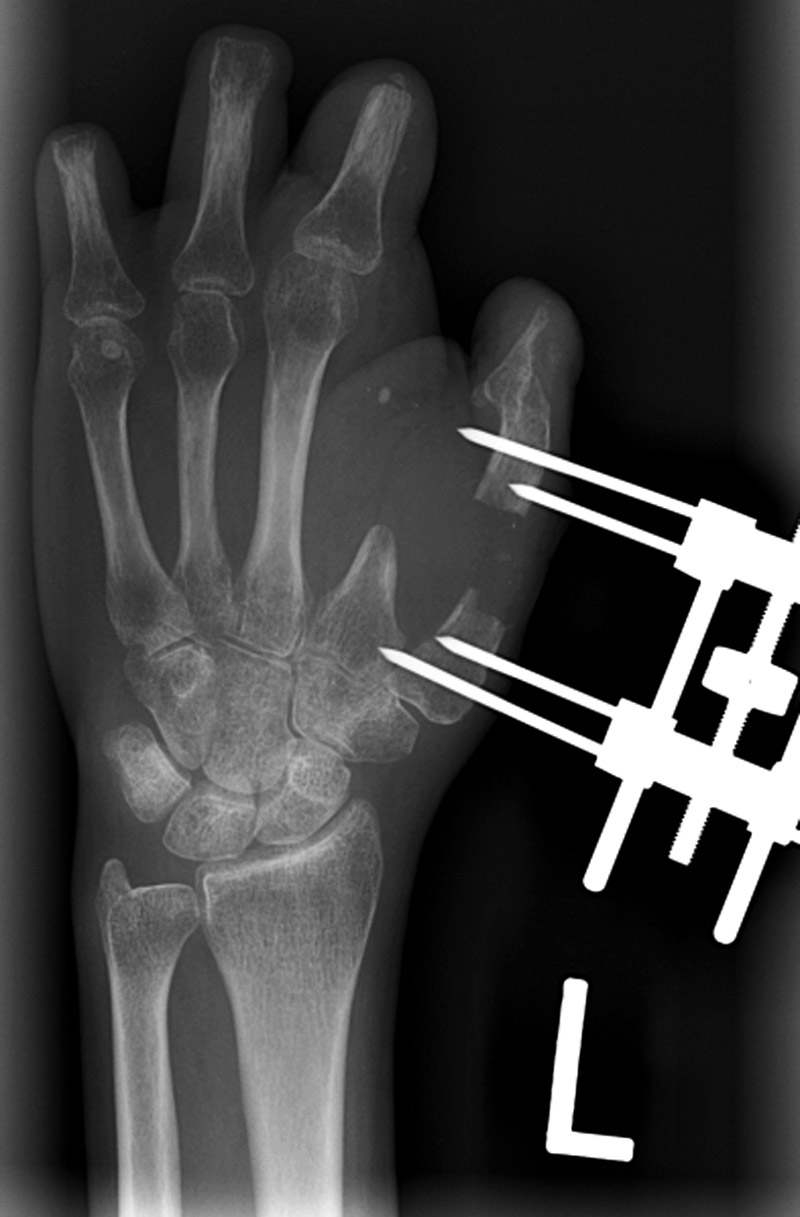

65 year-old woman with healing patellar fracture stabilized by two cancellous partially threaded bone screws and tension band wires.   External fixator used to treat a distal radius fracture (which also has a percutaneous pin in it). There are unilateral threaded pins in the radius and in the index finger metacarpal. From Hunter, 1994 From Taljanovic, 2005

This system is designed to stabilize otherwise unstable distal radius fractures. Image from Acumed The patient suffered a volar plate injury to his ring finger middle phalanx from an electrical shock while working on a fish tank!